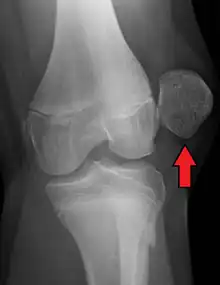

X-ray showing a patellar dislocation, with the patella out to the side.

A patellar dislocation is a knee injury in which the patella (kneecap) slips out of its normal position.[5] Often the knee is partly bent, painful and swollen.[1][2] The patella is also often felt and seen out of place.[1] Complications may include a patella fracture or arthritis.[3]

A patellar dislocation typically occurs when the knee is straight and the lower leg is bent outwards when twisting.[1][2] Occasionally, it occurs when the knee is bent and the patella is struck directly.[1] Commonly associated sports include soccer, gymnastics, and ice hockey.[2] Dislocations nearly always occur away from the midline.[2] Diagnosis is typically based on symptoms and supported by X-rays.[2]